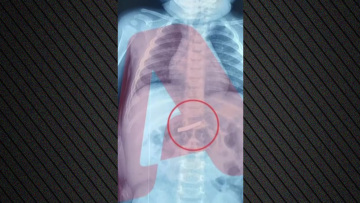

Την αγωνία όσων δουλεύουν στο σύστημα υγείας να μην χαθεί κανείς από την αλυσίδα σωτηρίας των ασθενών, εκφράζει η συντονίστρια & διευθύντρια της 7ης πνευμονολογικής κλινικής του νοσοκομείου «Σωτηρία» Μίνα Γκάγκα, όπου νοσηλεύονται ασθενείς με πνευμονίες λόγω κορωνοϊού. Μιλώντας στο Αθηναϊκό Πρακτορείο Ειδήσεων, τονίζει πως «κάθε εκπαιδευμένος επαγγελματίας υγείας που λείπει από τη νοσηλευτική αλυσίδα είναι πρόβλημα και κίνδυνος για όλη την αλυσίδα και τους ασθενείς».

Η κ. Γκάγκα κάνει λόγο για αυστηρά πρωτόκολλα που μπαίνουν σε εφαρμογή όταν έρχονται σε επαφή με ασθενή που νοσεί από κορωνοϊό: «Προσέχουμε ακόμα και τον τρόπο που βγάζουμε τα βρώμικα ρούχα, για να μην κινδυνέψουμε εμείς αλλά και κανείς άλλος. Πρέπει στους αναπνευστικούς ασθενείς να παρακολουθούμε συνεχώς το οξυγόνο τους και να προσαρμόζουμε ανάλογα την οξυγονοθεραπεία ή και την υποστήριξη της αναπνοής».

Η κυρία Γκάγκα, που είναι μέλος ΔΣ της global health alliance against respiratory disease του ΠΟΥ, τονίζει ότι η έγκαιρη αγωγή είναι σημαντική στις πνευμονίες και στους νοσηλευόμενους, γι' αυτό και «αρχίζουμε άμεσα αγωγή» και συμπληρώνει πως οι καπνιστές και οι άρρωστοι με ΧΑΠ είναι συνήθως πιο επιρρεπείς σε λοιμώξεις του αναπνευστικού και πνευμονίες.

«Νοσηλεύουμε και σαραντάρηδες και πενηντάρηδες. Κάποιοι έχουν παράγοντες κινδύνου, κάποιοι είναι απολύτως υγιείς ή ακόμα και αθλητές. Σίγουρα, η κατάσταση του ανοσοποιητικού έχει σημασία και υπάρχουν ευπαθείς ομάδες, αλλά νομίζω κανείς δεν είναι άτρωτος».